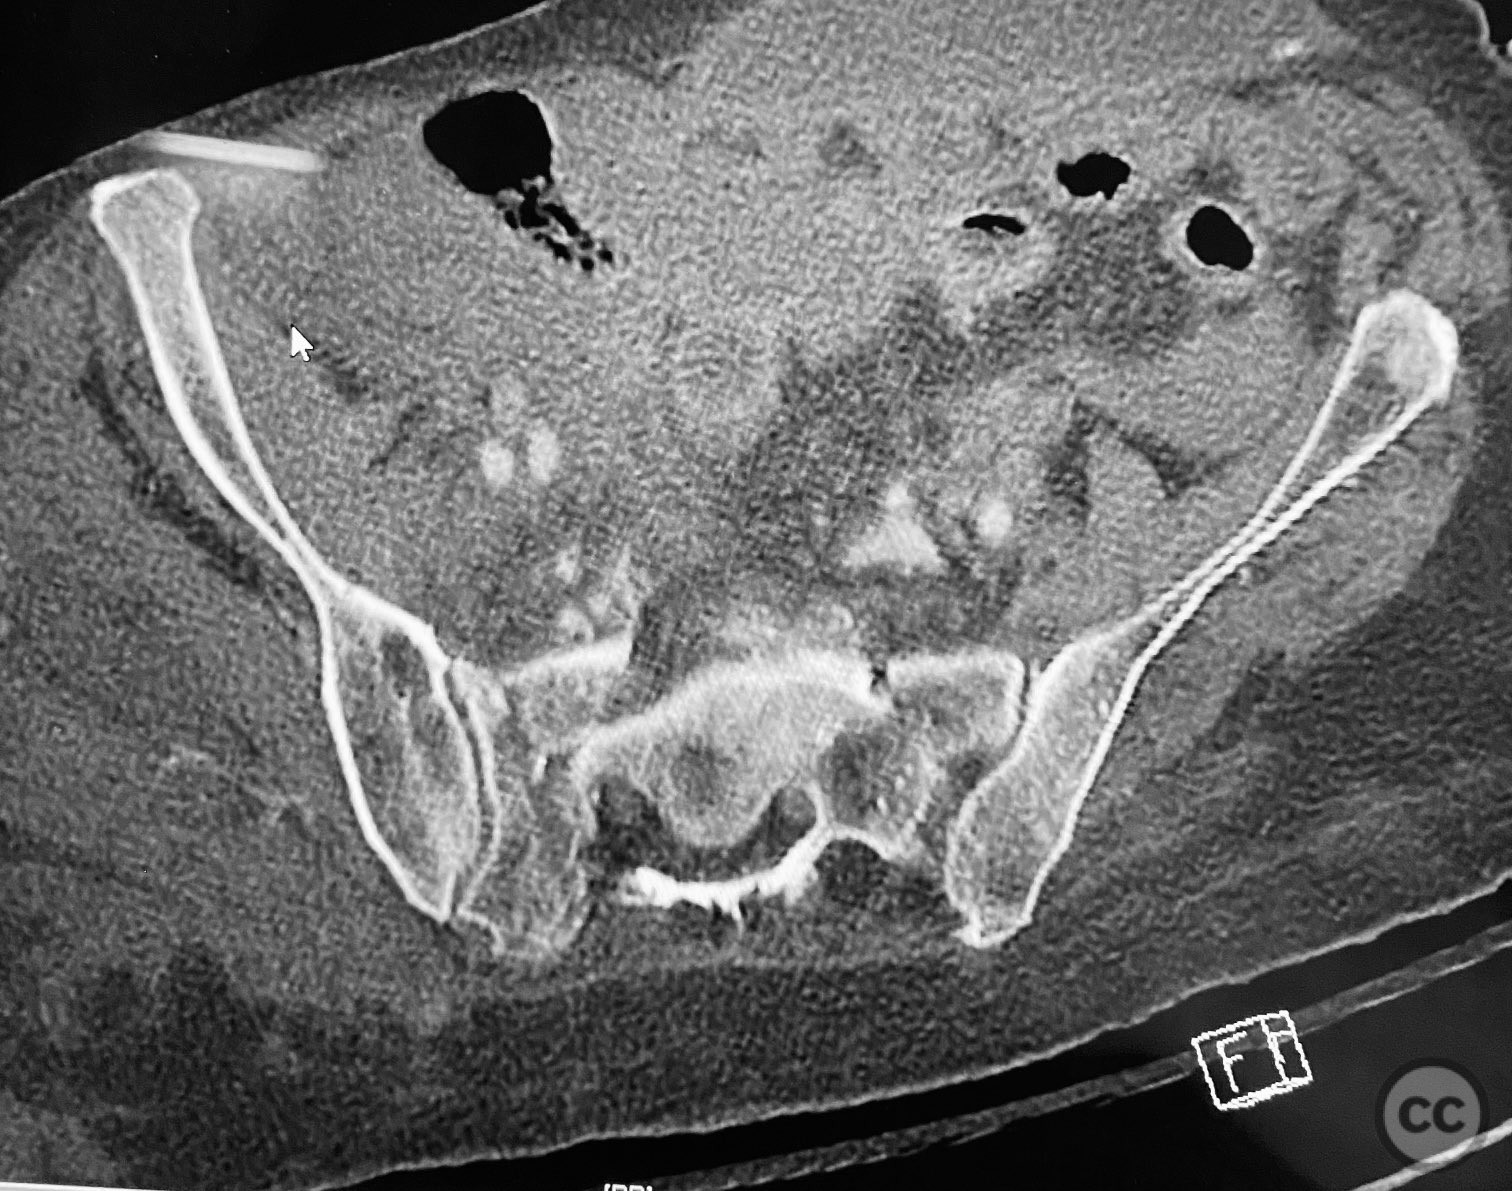

Clinical and radiological findings:  An elderly patient sustained multiple traumatic injuries, including complex unstable pelvic ring disruption (AO/OTA 61-C, likely C1 or C2 based on instability and comminution), comminuted proximal femoral fracture (AO/OTA 31-A3 or 31-B, depending on trochanteric or neck involvement), and significant abdominal trauma necessitating intra-abdominal packing. Initial clinical evaluation revealed hemodynamic instability and poor bone quality consistent with advanced age. Distal femoral traction was applied for provisional reduction. Radiological assessment was limited by osteopenia, fracture comminution, and the presence of abdominal packing materials.

Planning remarks:  The preoperative plan included early closed reduction maneuvers under fluoroscopic guidance, percutaneous stabilization of the pelvic ring with cannulated screws, and intramedullary nailing of the proximal femur. The anatomical approach for pelvic fixation was percutaneous iliosacral screw placement; for the femur, a standard antegrade intramedullary nailing technique was planned.

Anatomical surgical approach:  Percutaneous iliosacral screw fixation was performed through small lateral gluteal incisions, with blunt dissection to the outer table of the os ilium. Under fluoroscopic guidance, guidewires were advanced across the sacroiliac joint into the S1 body, followed by cannulated screw insertion. For the proximal femur, a longitudinal incision was made proximal to the greater trochanter, splitting the fascia lata and gluteus medius fibers to access the piriformis fossa. A guidewire was inserted into the medullary canal, followed by sequential reaming and insertion of an intramedullary nail.

Intraoperative imaging was challenging due to osteopenic bone, fracture comminution, and interference from abdominal packing. Accurate identification of safe osseous corridors for iliosacral screw placement required multiple fluoroscopic projections and careful attention to pelvic landmarks. Bone quality necessitated cautious screw advancement to avoid iatrogenic cortical breach. After pelvic fixation, intramedullary nailing of the proximal femur proceeded without complication. Abdominal packing was removed and laparotomy wound closed after skeletal stabilization. Early mechanical stabilization of both pelvic and femoral injuries was prioritized to optimize survivability in this multiply injured elderly patient.